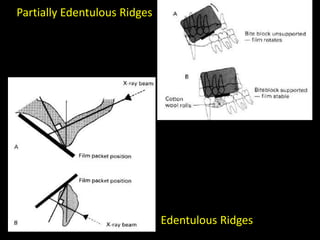

3. Special considerations for intra-oral radiography include techniques for mandibular third molars, gagging patients, endodontic procedures, edentulous ridges, and pediatric patients.